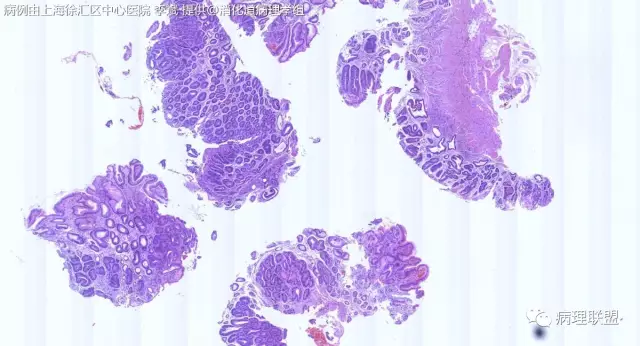

F-56 胃窦粘膜活检(低级别 vs 高级别)

女,56岁,胃窦粘膜活检(病例由上海徐汇区中心医院 李斌 提供,致谢!)

病例讨论

考虑:低级别上皮内病变(轻度异型增生)。

@李斌,高级别,腺体结构乱复杂,核异型性大,极向乱